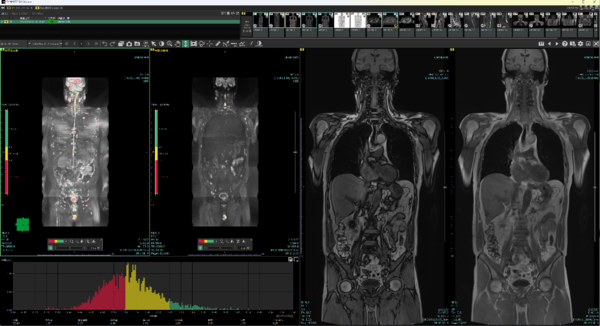

Body DWIビュー(MR)のレイアウト画面

Body DWIビュー(MR)での自動スティッチング機能および自動信号値補正機能。

骨抽出機能の例。骨転移検索目的での読影効率化に繋がることが期待できる。